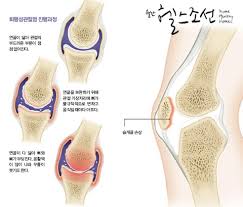

무릎 연골 손상 증상은 여러 가지 원인이 있습니다. 특히 젊은 층은 외상이나 과격한 운동 중에 손상을 입을 가능성이 크며, 중장년층은 노화로 인한 퇴행성 변화가 원인이 됩니다. 갑작스럽게 무릎의 방향을 바꾸거나 외부의 충격이 가해질 때도 무릎 연골 손상 증상이 나타날 수 있습니다. 이러한 원인들은 무릎의 구조적 안정성을 해칠 수 있으며, 결과적으로 무릎 연골 손상 증상이 심해지게 됩니다.

무릎 연골 손상 증상은 단순한 무릎 통증으로 끝나지 않고 다양한 동반 증상과 함께 나타납니다. 일반적으로 무릎 부위의 붓기와 불편함이 동반되며, 특히 무릎의 안쪽이나 바깥쪽에서 통증이 느껴질 수 있습니다. 또한, 무릎을 움직일 때 '잠김 현상'이 발생하기도 하며, 이는 무릎 연골 손상 증상이 심한 경우 나타나게 됩니다. 이러한 증상들은 운동 후나 오랜 시간 앉아 있다가 일어날 때 더욱 심해질 수 있습니다.